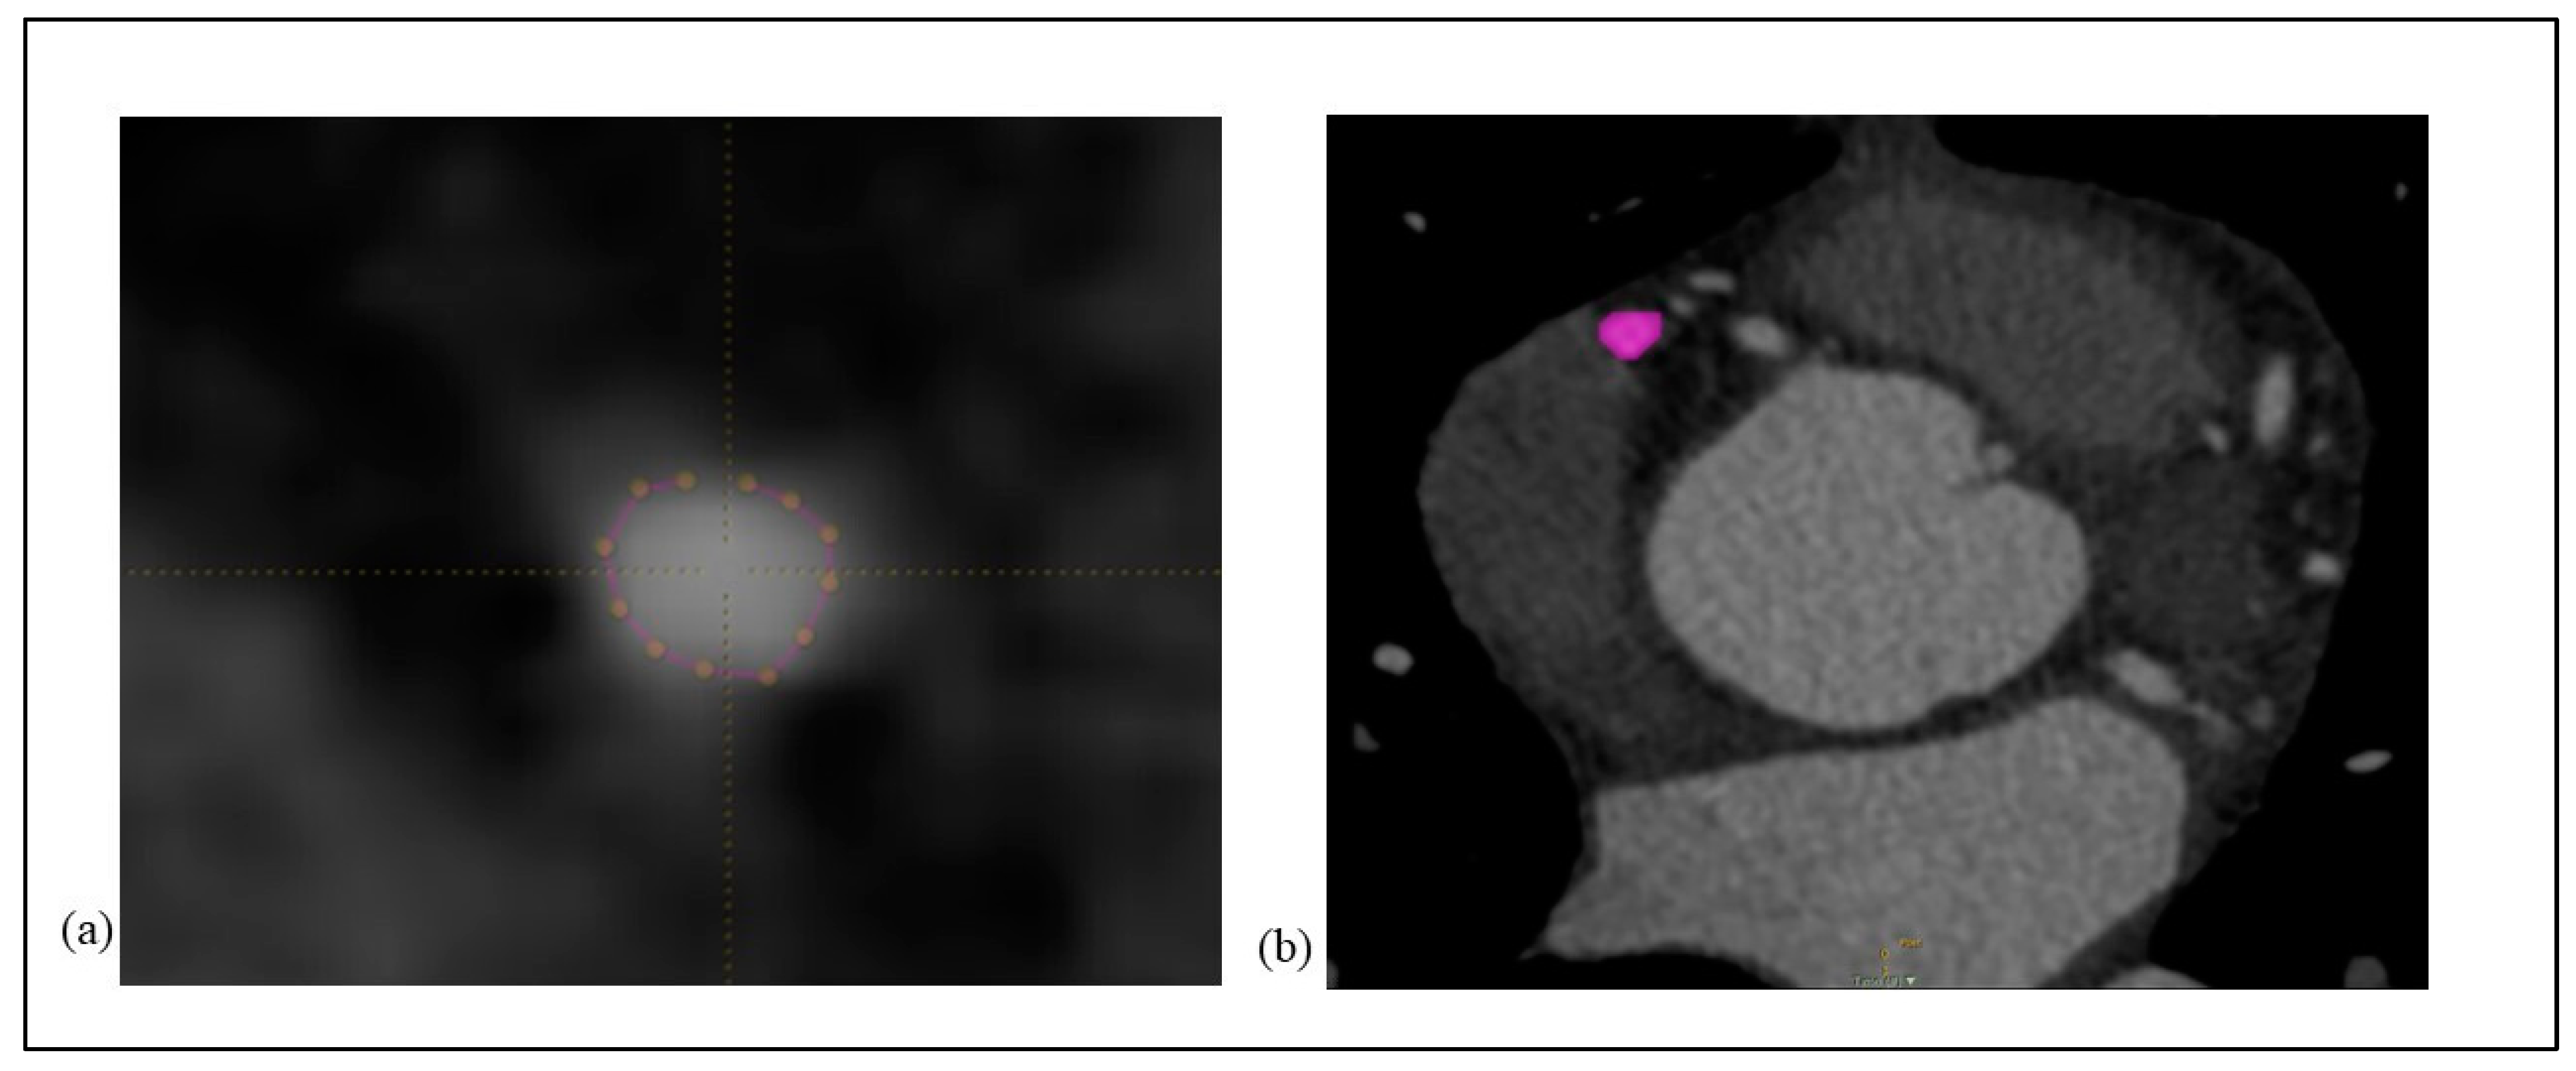

2.1. Manual Segmentation (Pencil 2D Technique) Protocol

2.2. Semiautomatic Segmentation (Circle 3D Technique) Protocol